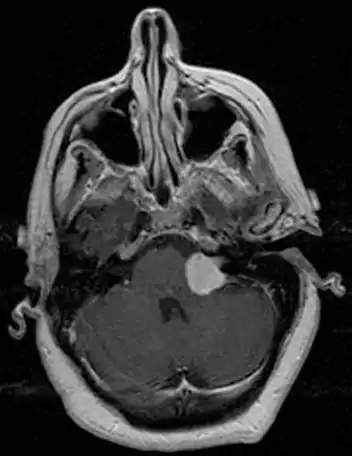

MRI scan is the imaging of choice because it can more accurately differentiate the mass from other tumors such as meningioma, facial nerve schwannoma, epidermoid cyst, arachnoid cyst, aneurysm, and brain metastasis. MRI scan also helps in surgical planning and follow-up of the tumor after surgery.[19] VC is usually isointense on T1 weighted images, hyperintense on T2 weighted images, and enhances after given gadolinium contrast.[20] The use of MRI however should be used appropriately as patients with unilateral tinnitus alone